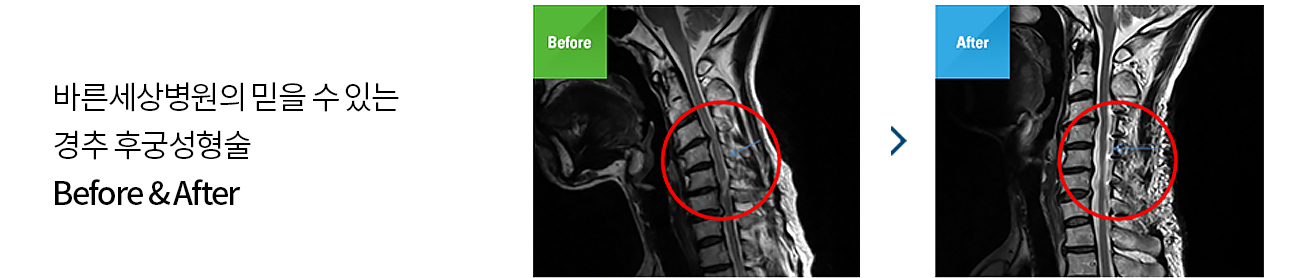

여러 마디의 경추 협착증이나 인대골화증으로

척추신경 손상이 있는 경우의 치료법

후궁이라는 뼈는 목뼈의 척수신경이 지나가는 부위의 뚜껑에 해당하는 뼈입니다. 이 부위를 열어 눌린 척수신경을 풀어줍니다.

뚜껑을 여는 수술작업이 후궁의 모양을 정상적으로 성형한다 하여 후궁성형술이라고 합니다.

후종인대 골화증이 심해 경추 척수증으로 진단될 경우 경추 후궁성형술로 치료하게 됩니다.